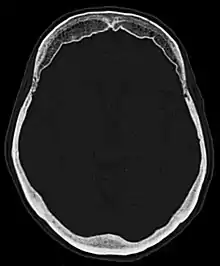

Hyperostosis frontalis interna

Hyperostosis frontalis interna is a common, benign thickening of the inner side of the frontal bone of the skull. It is found predominantly in women after menopause and is usually asymptomatic. Mostly frequently it is found as an incidental finding discovered during an X-ray or CT scan of the skull.

| Hyperostosis frontalis interna in a 74-year-old woman | |

Hyperostosis frontalis at CT